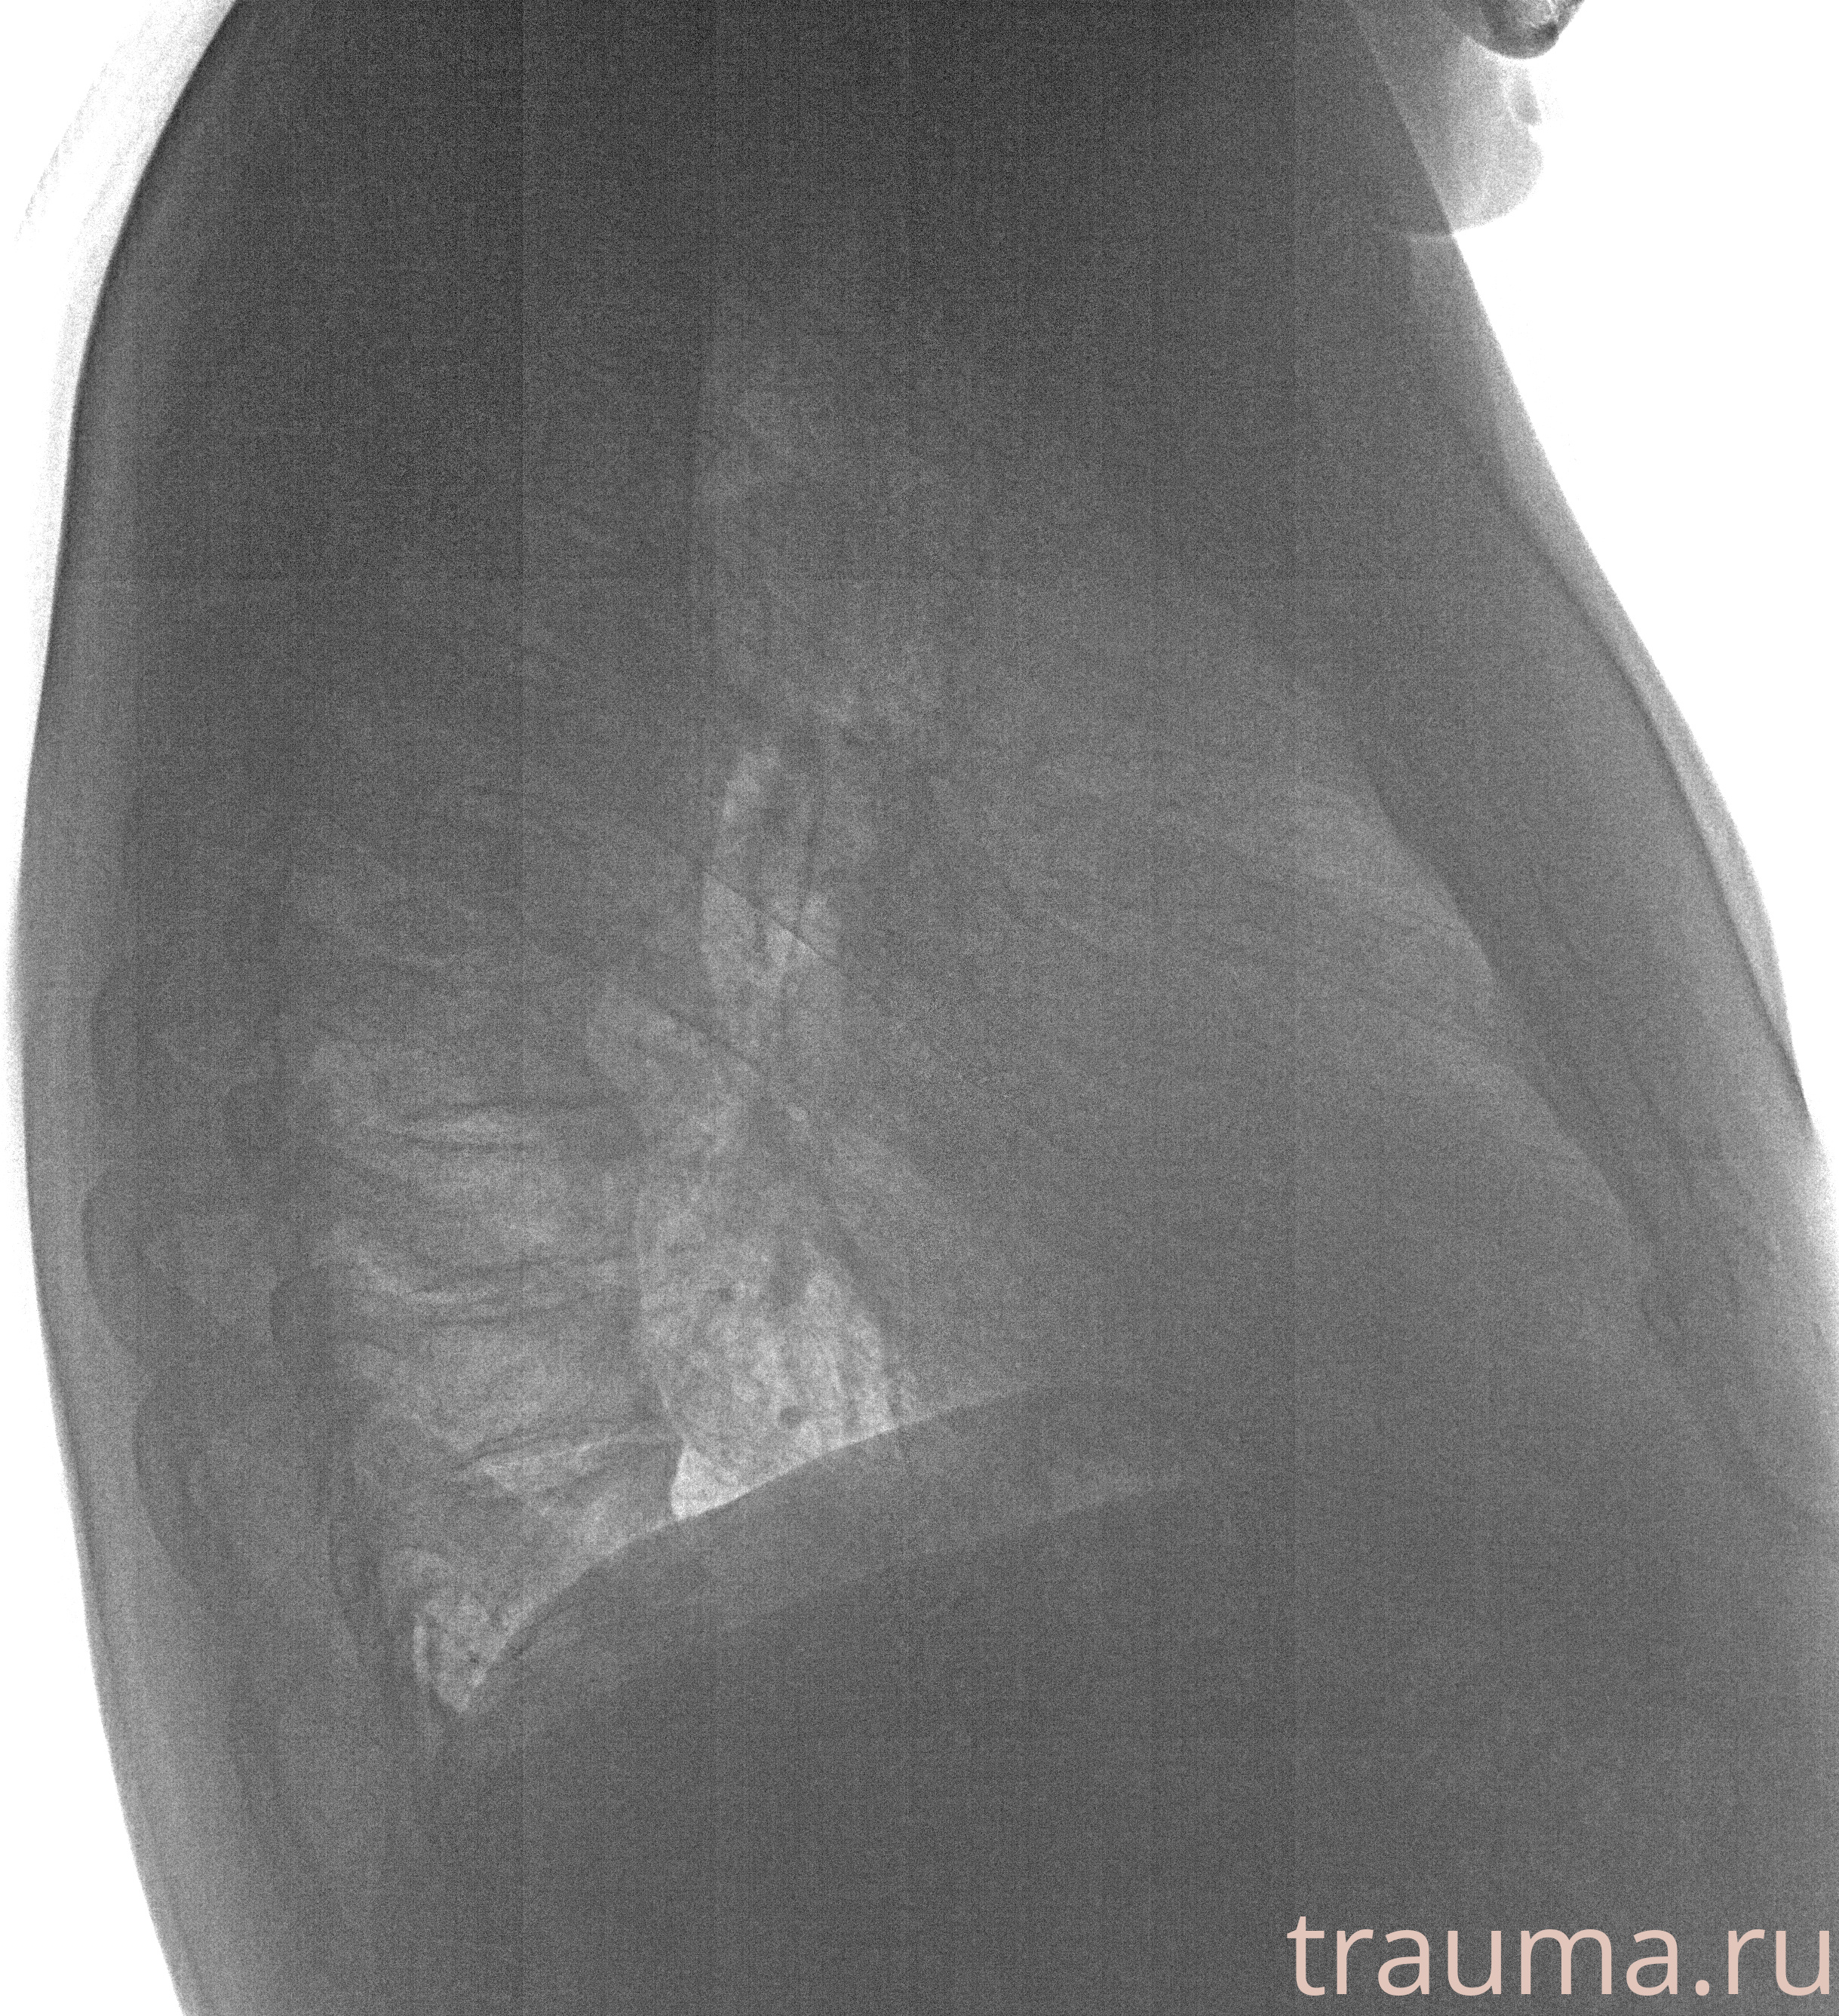

Рентгенограммы

Рентген на дому: по вашему адресу приезжает врач-рентгенолог, травматолог-ортопед с мобильным рентгеновским аппаратом, проводит диагностику травмы или заболевания, делает необходимые рентгенограммы, дает рекомендации по дальнейшему лечению. Получить качественные снимки в домашних условиях возможно благодаря уникальной методике, разработанной МосРентген Центром для института  Склифосовского